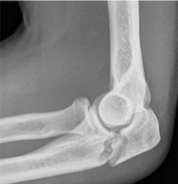

Tipo de fractura en la clasificacion de Mayo

1a (no desplazada, no conminutada)

2a (Desplazada estable, no conminutada)

3b (Desplazada inestable (por la luxacion) y conminutada)

Tratamiento de esta fractura

Conservador

Inmovilizar con yeso o ferula a 45-90°, inicio gradural de movilizacion a las 4 semanas

Obenque con clavillos de kirschner y alambre

Trtamiento de esta fractura

Fijacion con placa y tornillos (por multifragmentada)